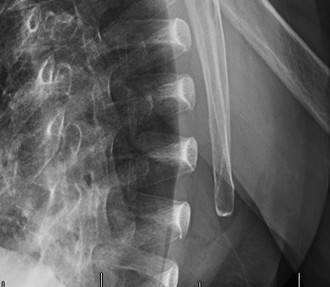

A sophomore, high school wide receiver presents to your clinic at the beginning of his football season. He reports a dislocation event after being tackled; his shoulder was “put back in place” by the on-field athletic trainer. A CT scan taken in the hospital today is shown (Fig. 2–33). He has been recruited by numerous colleges, plans to play at a division 1 school, and is very eager to return to the field.

Figure 2–33

The correct answer is (E). A large bony fragment (>20%) makes the failure rate with nonoperative treatment (Answers A, B) unacceptably high. This question is meant to illustrate the challenges associated with treating an in-season athlete and highlighting the indications for surgery after a first time dislocation event. Typically, early in a season, providers will initiate an aggressive PT program and try and return athletes to the field within a few weeks so that they can play out the remainder of the season. Towards the end of the season, when there is insufficient time to rehab a patient, one may choose early surgery so that the patient has maximal time to recover prior to the next season. In this case, even though the

patient is extremely motivated to return to the field and has only sustained a single dislocation event, the large bony Bankart lesion behooves surgical treatment. The best option for him would be to have early surgery and have a maximal amount of time to prepare for his senior season. A Latarjet procedure (Answer C) is used for patients with recurrent anterior instability and significant glenoid bone loss, and the Magnuson–Stack procedure (Answer D) is a largely historic procedure that was used for recurrent anterior instability. Objectives: Did you learn...? The common presentation of a patient with shoulder instability?